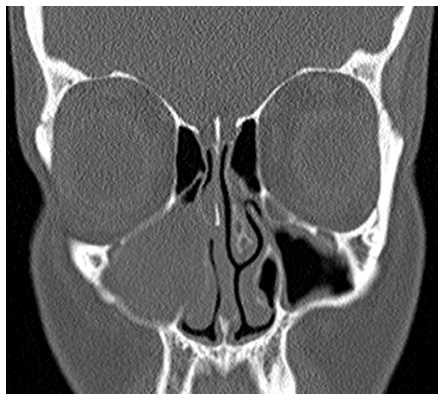

A 39year old Caucasian female presented with a few years history of progressive right sided nasal blockage with no associated history of epistaxis, headache or pain. She was a non-smoker and otherwise fit and well. On examination, there was decreased air entry on the right side. Nasal endoscopy revealed a straight nasal septum but the right nasal cavity was smaller compared to the left side. Endoscopically, no intranasal lesion was identified but because of the bulge in the right lateral nasal wall, a computed tomogram (CT) of her paranasal sinuses was arranged. The CT scan revealed soft tissue opacity in the right maxillary sinus with expansion of the sinus into the right nasal cavity but no evidence of bony erosion (Figures 1&2).

Figure 1 CT shows maxillary sinus tumour pushing the right lateral nasal wall medially.